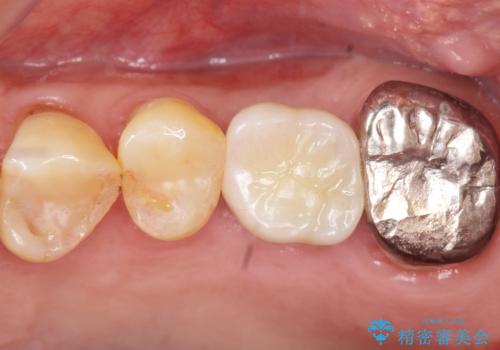

審美的・機能的な仕上がりに喜んで下さいました。

また、半年という比較的短期間でインプラント治療が終わったことにもご満足頂けました。

インプラントの種類:スプライン ツイスト (保証期間:5年)

クラウンの種類:ベレッツァクラウン (オールセラミック)

固定様式:セメント固定